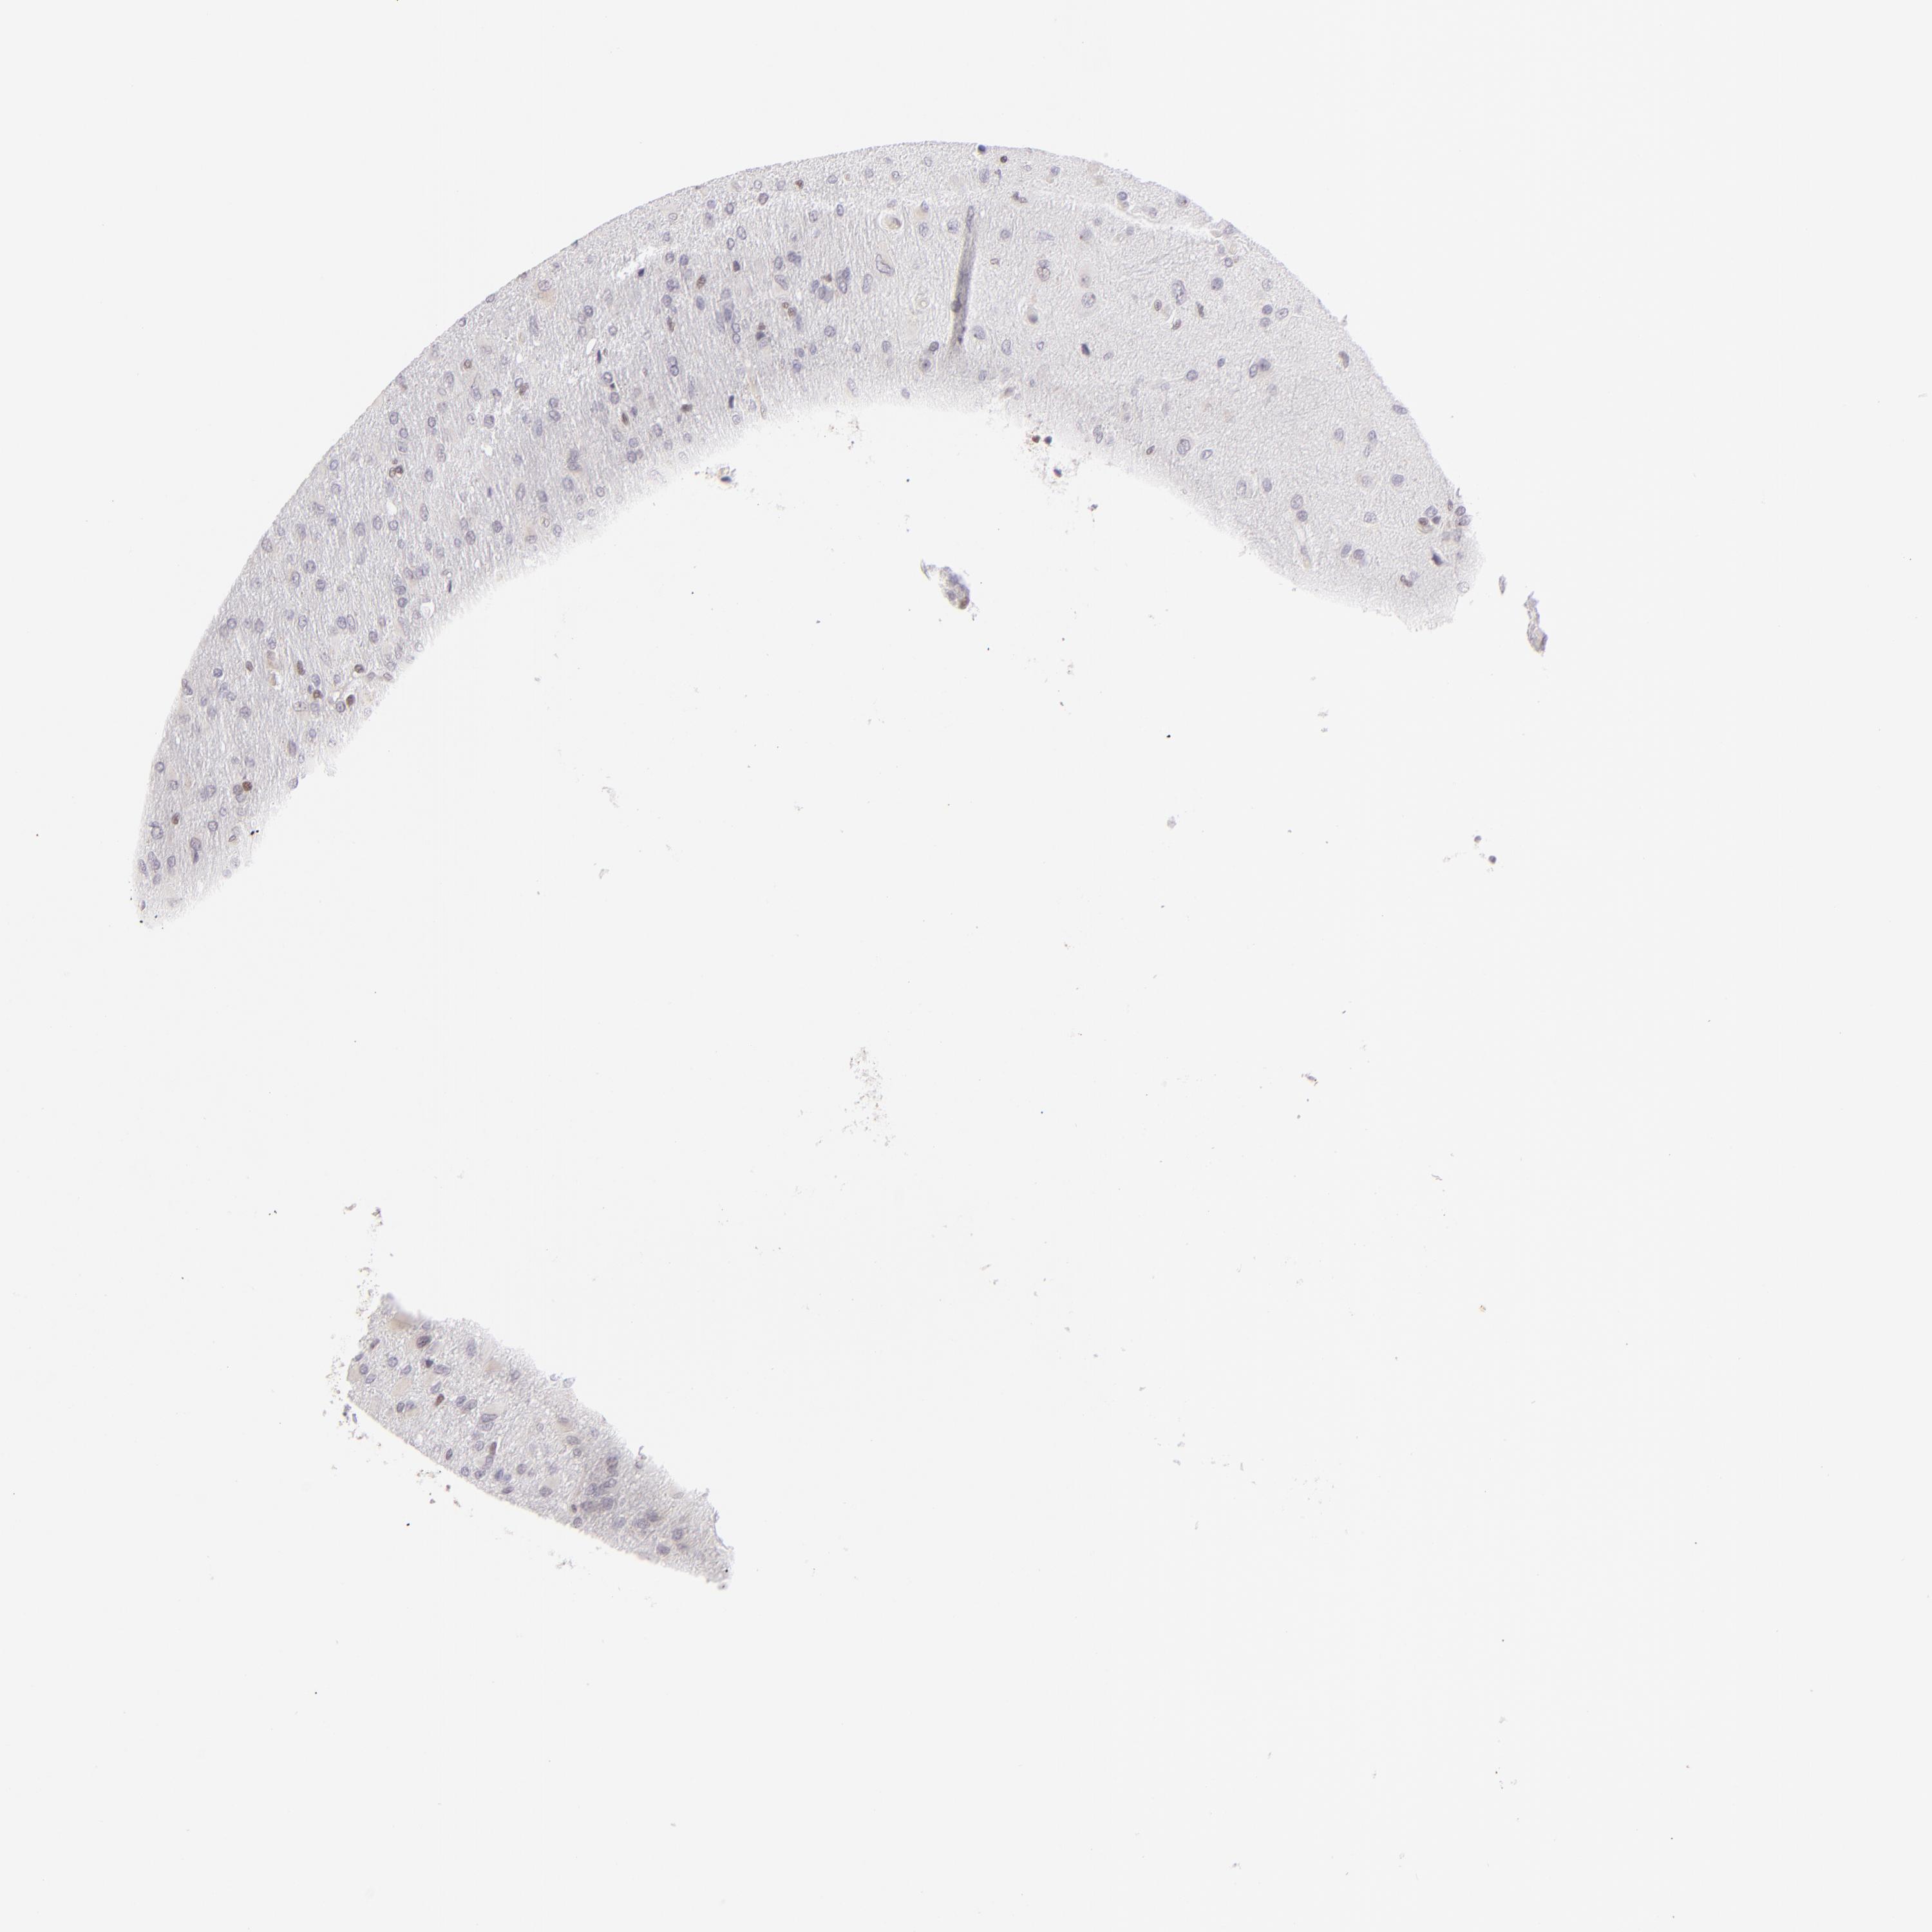

GLIOMA - Protein expressioni

A mouse-over function shows sample information and annotation data. Click on an image to view it in a full screen mode. Samples can be filtered based on level of antibody staining by selecting one or several of the following categories: high, medium, low and not detected. The assay and annotation is described here.

Note that samples used for immunohistochemistry by the Human Protein Atlas do not correspond to samples in the TCGA dataset.

Antibody stainingi

Antibody staining in the annotated cell types in the current human tissue is reported as not detected, low, medium, or high, based on conventional immunohistochemistry profiling in selected tissues. This score is based on the combination of the staining intensity and fraction of stained cells.

Each image is clickable and will lead to virtual microscopy that enables deeper exploration of all samples and also displays staining intensity scores, fraction scores and subcellular localization as well as patient and tissue information for each sample.

Antibody HPA064323

Antibody CAB002608

Glioma, malignant, Low grade

Glioma, malignant, High grade